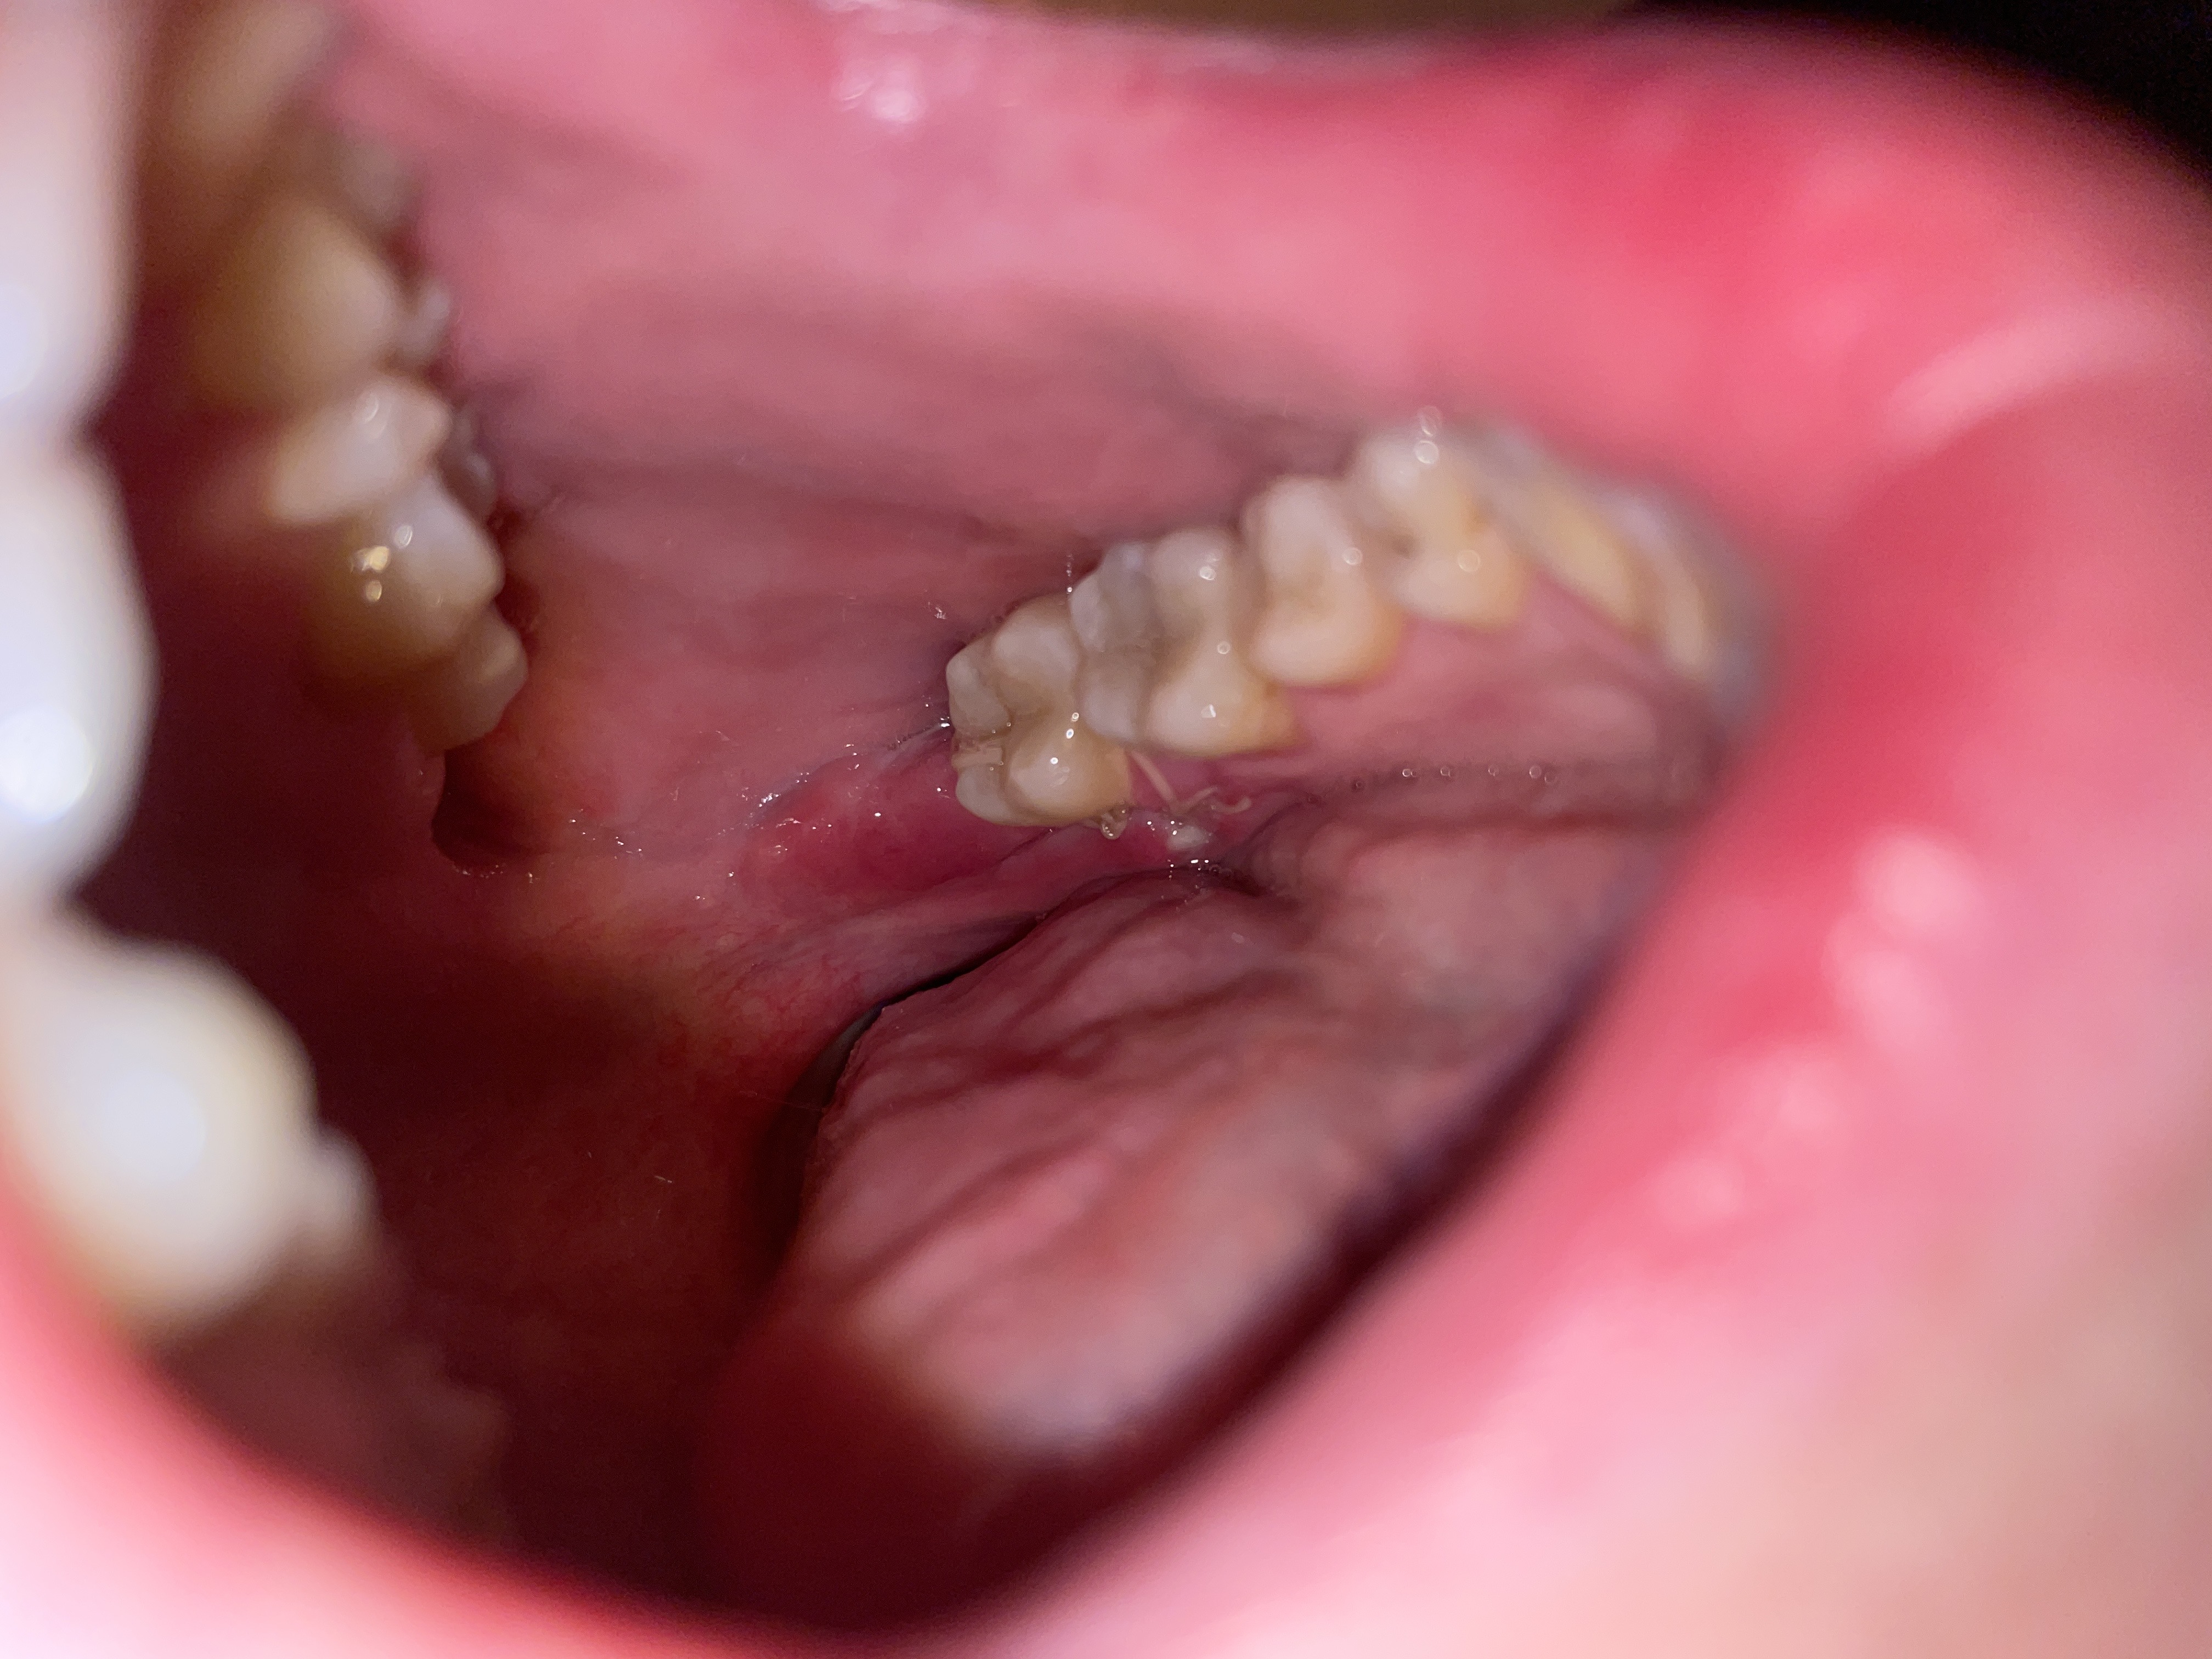

Hij zei direct dat er een stuk bot zichtbaar is (ik vermoed wat je op de foto ziet). Daarna zei hij dat de randen ontstoken zijn. Vervolgens drukte hij nog op de binnenkant (foto 1). Dit deed echt zeer.

Daarnaast dat bot wat zichtbaar is op foto 1, geneest dat vanzelf? Gaat dat goed?